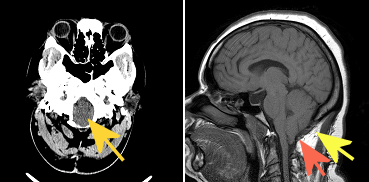

Figure 1: (A) non contrast head CT with parenchymal fullness in the region of the foramen magnum due to the low lying position of the cerebellar tonsils (orange arrow). (B) Sagittal non contrast T1 weighted brain MRI redemonstrates the low lying position of the cerebellar tonsils more than 5 mm below the expected position of the foramen magnum (red arrow). There has been a suboccipital crainectomy (yellow arrow).

Diagnosis: Chiari 1 malformation